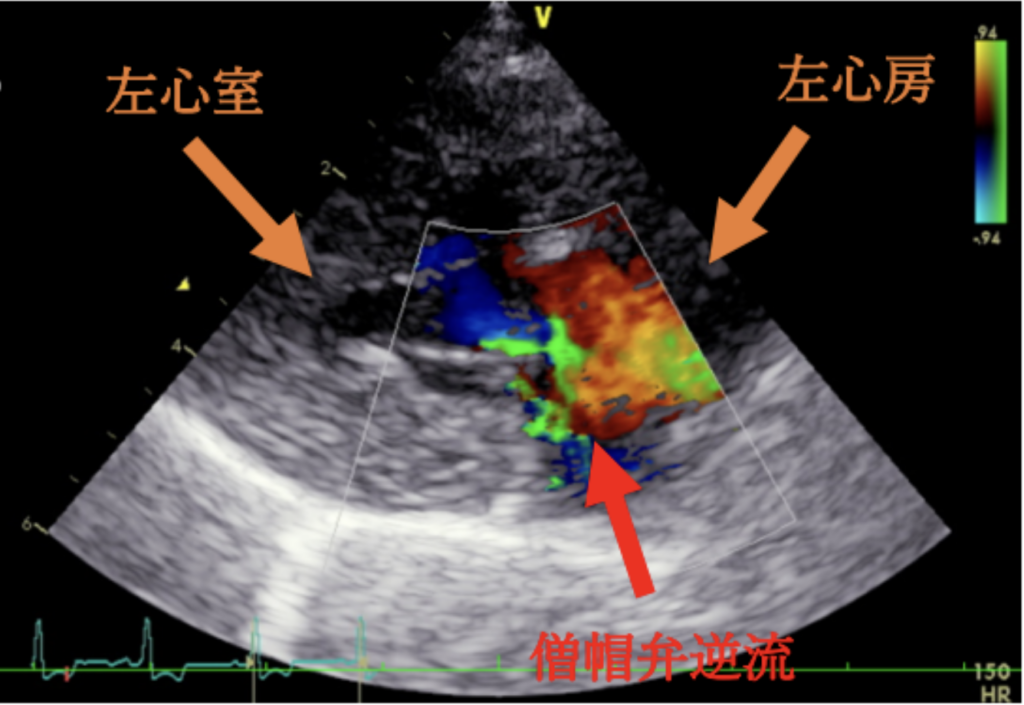

今回の⼼臓超⾳波検査では、僧帽弁からの⾎液の逆流が以前よりも増えており、⼼臓が

拡⼤してきていることが確認されました。そのため、⼼臓の働きを助けて病気の進⾏を

遅らせる⽬的で、ピモベンダンというお薬の内服を始めることになりました。

粘液腫様僧帽弁疾患とは、この僧帽弁がしっかり閉まらなくなり、⾎液が逆流してしま

う病気です。初期には症状が出ないこともありますが、進⾏すると⼼臓が⼤きくなり、